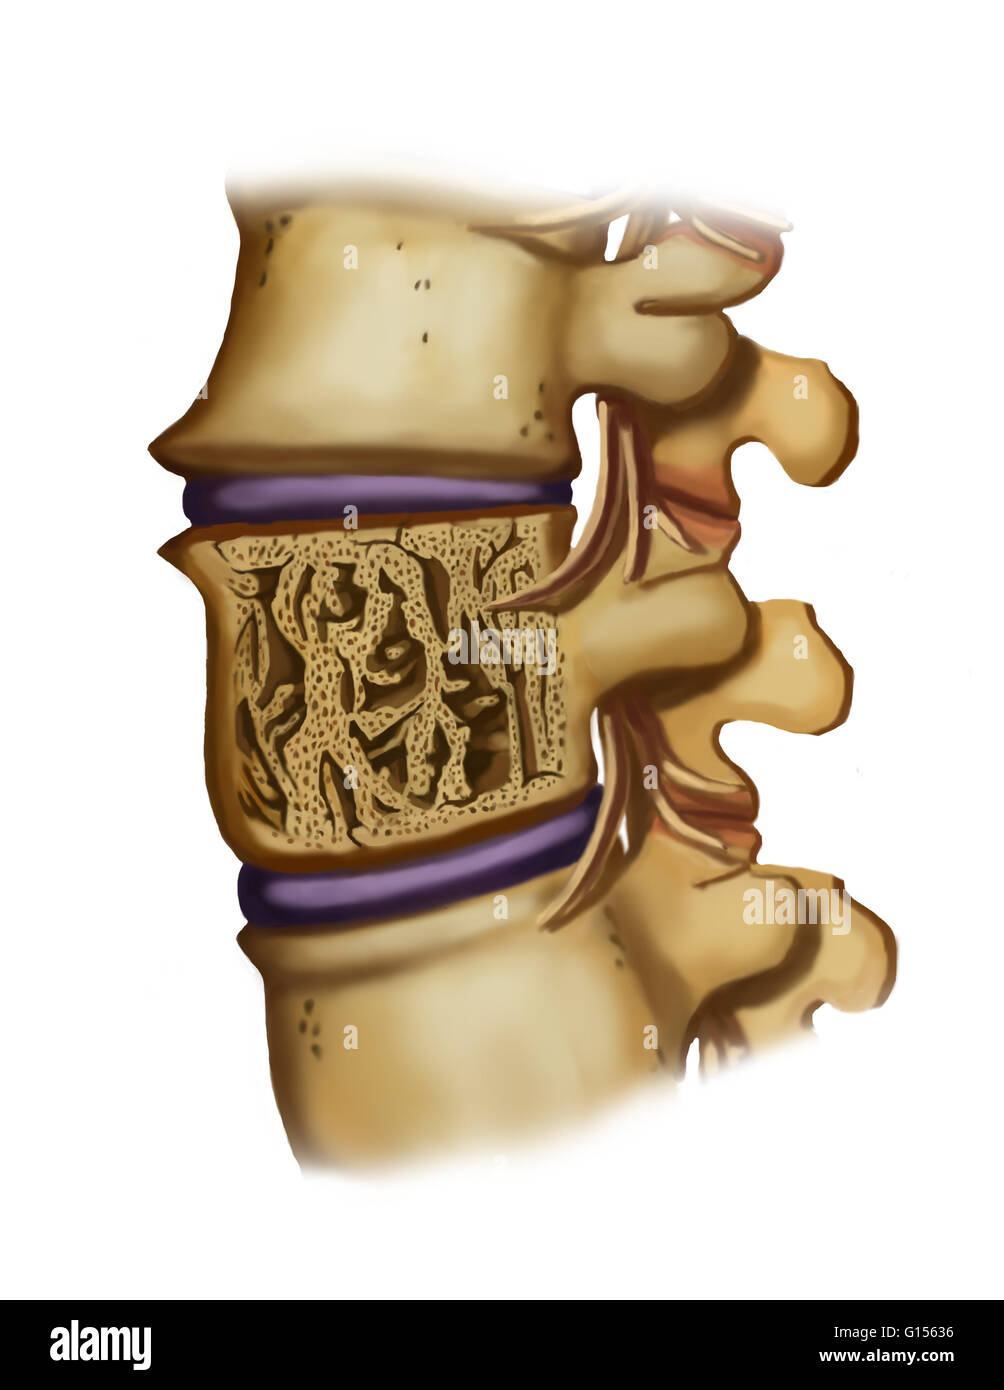

Brittle Bones Spine . The thinning bones can collapse during normal activity, leading to a spinal fracture. These compression fractures can cause a great deal of pain and can permanently alter the shape and strength of the spine. Osteoporosis causes bones to thin and become more brittle and weak. Bone loss speeds up significantly after age 60, and if you don't do anything about it (especially if you have osteopenia), the loss. Healthy bones are dense and strong. Osteoporosis is a condition that causes your bones to become thinner, weaker, and more brittle. Osteoporosis is a “silent” disease because you may not have symptoms. This increases your risk of broken bones (fractures). Some bone loss as you age is normal, but if you lose too much, you can develop osteoporosis, resulting in brittle bones. Osteoporosis causes bone density and quality to deteriorate over time. Medical treatment can help slow or stop bone loss. Spine osteoporosis causes the bones in a person’s spine to become brittle, leaving them vulnerable to fracturing. Osteoporosis is a disease that causes bones to become weak and brittle. According to the international osteoporosis foundation, it affects 21.2% of women over age 50 and.

Brittle Bones Spine Osteoporosis causes bone density and quality to deteriorate over time. Osteoporosis is a condition that causes your bones to become thinner, weaker, and more brittle. Medical treatment can help slow or stop bone loss. Osteoporosis causes bone density and quality to deteriorate over time. Osteoporosis is a “silent” disease because you may not have symptoms. Healthy bones are dense and strong. The thinning bones can collapse during normal activity, leading to a spinal fracture. Spine osteoporosis causes the bones in a person’s spine to become brittle, leaving them vulnerable to fracturing. This increases your risk of broken bones (fractures). Osteoporosis causes bones to thin and become more brittle and weak. Bone loss speeds up significantly after age 60, and if you don't do anything about it (especially if you have osteopenia), the loss. Some bone loss as you age is normal, but if you lose too much, you can develop osteoporosis, resulting in brittle bones. According to the international osteoporosis foundation, it affects 21.2% of women over age 50 and. These compression fractures can cause a great deal of pain and can permanently alter the shape and strength of the spine. Osteoporosis is a disease that causes bones to become weak and brittle.